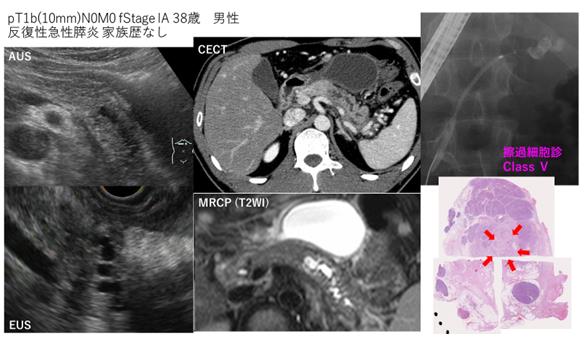

該患者因反復發生急性胰腺炎而被懷疑患有胰腺癌,我被送往醫院。檢查顯示胰腺中的腫瘤為10mm,胰管也擴張。